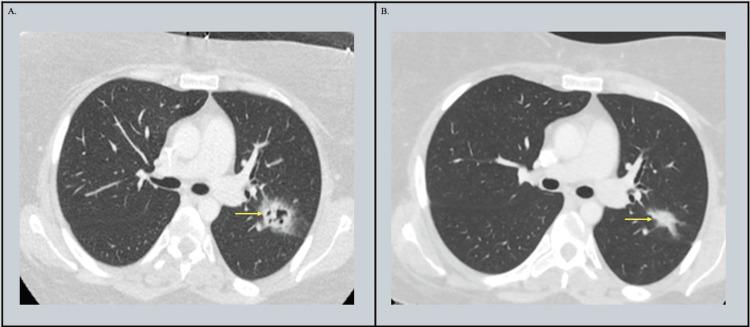

Legionella maceachernii Pneumonia Presenting as a Cavitary Lesion in an Immunocompromised Patient.

is an intracellular, gram-negative bacterium known as a less common cause of pneumonia, which has become a public health concern in recent years due to increased incidence. is recognized as the most common cause of Legionnaires' disease. Other species, including , have been rarely described as causes of Legionnaires' disease. Moreover, cavitary lesions as radiological findings in patients with Legionnaires' disease are uncommon but have been reported, especially in immunocompromised patients. Although the gold standard for diagnosis is a positive culture, the need for special media and extended time for growth can overlook or delay diagnosis. Additionally, urine antigen testing will miss detection of species other than serogroup 1. Molecular testing, although not routinely performed, is a promising tool for early detection and identification of other species. We present a case of an immunocompromised patient presenting with fevers and a cavitary lesion, diagnosed with through cell-free DNA sequencing.